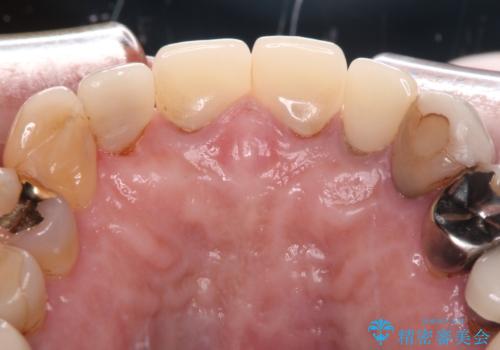

- 前歯が土台ごと外れてしまったとのことで来院された患者様です。

土台は外れていましたが破折などの問題はなく、土台からの再治療で対応可能な状態でした。

隣の犬歯も神経が取り除かれていたしたが、ラミネートベニアで治療されており、裏側でむし歯が進行する可能性があったため、こちらも治療が必要と判断されました。

今回の治療を機会に前歯全体をやり直すことも考えたそうですが、取り急ぎ要治療となった2歯を先に治療することとしました。